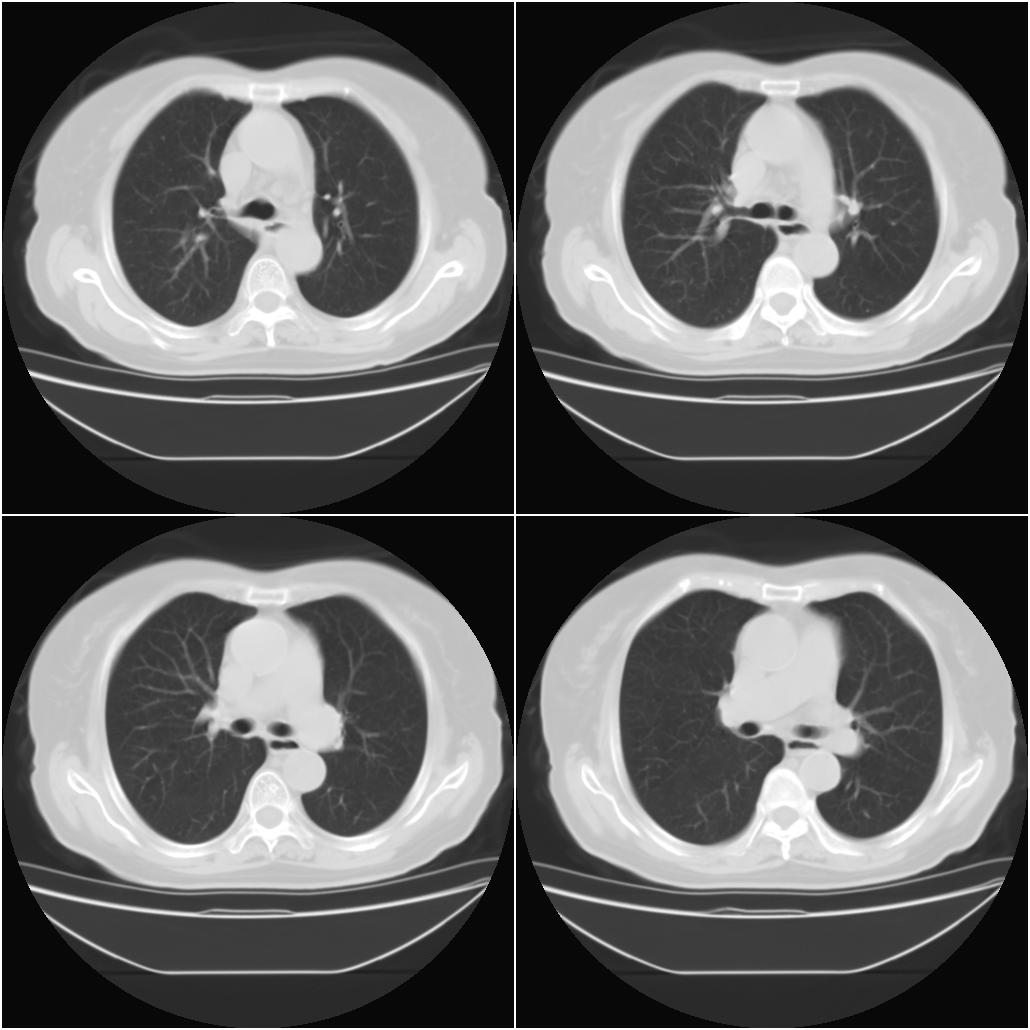

以下是引用sxlcbc在2007-12-23 4:27:00的发言:[br]气管源性肿瘤觉得有点不靠谱啊,看上去气管是受压改变的。更像是上段食管的改变,周围淋巴结肿大,食管受压。看看以下六幅图片:[br]不过,有一点不好理解:食管肿瘤应该有食道症状的,再说食管癌出现周围这么大的淋巴结也不多见啊,如果考虑淋巴瘤倒是更合理一点,这样气管,食管受压改变也许更合理一些。[br][br]